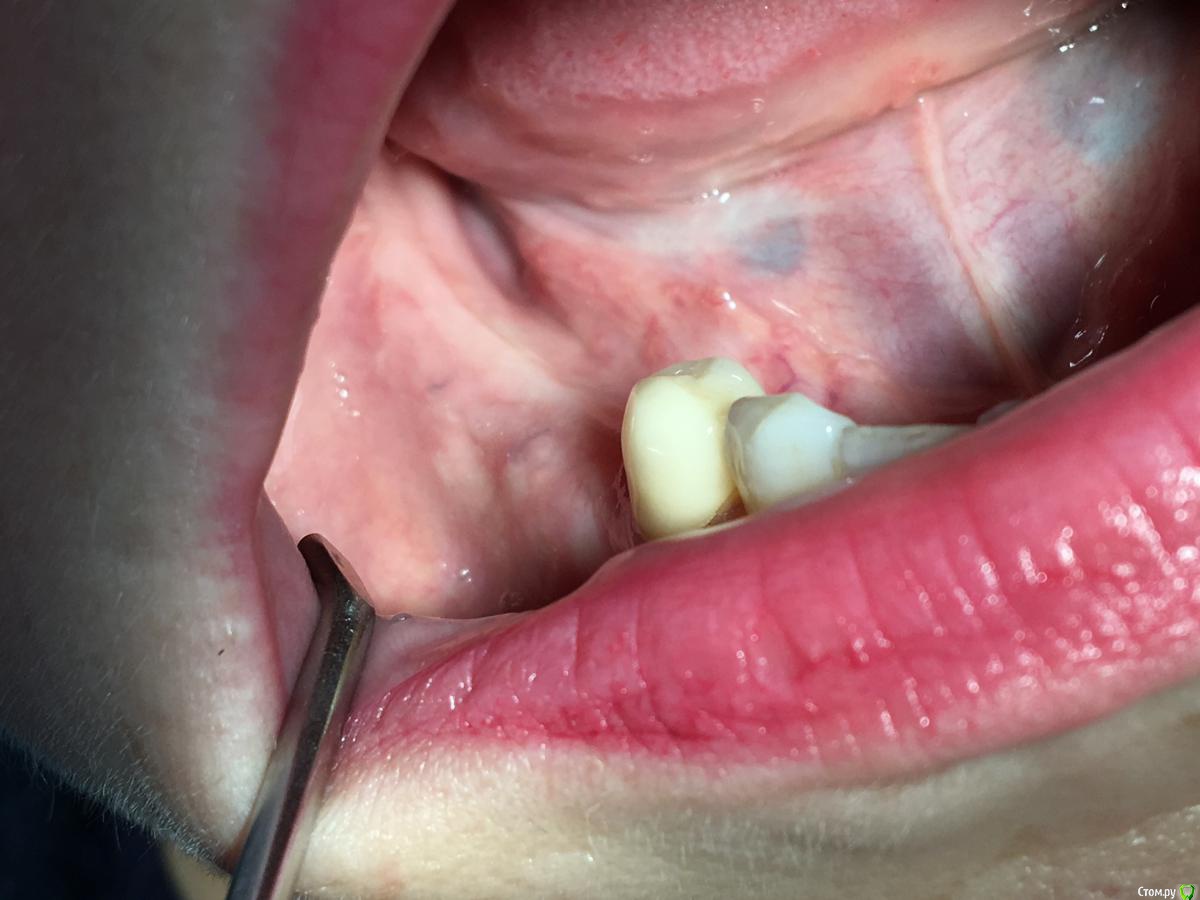

Shakirbura Опубликовано 8 ноября, 2017 Поделиться Опубликовано 8 ноября, 2017 Здравствуйте, коллеги!Раскрыл через 5 месяцев после нкр. Поверхностный слой материала легко соскреб распатором. Глубоко ковырять не стал. Был апатос микс + ауто 60/40. Почему такая картина, кто может подсказать?Есть надежда, что это станет костью? Ссылка на комментарий

kriokov Опубликовано 9 ноября, 2017 Поделиться Опубликовано 9 ноября, 2017 1 фотка в теме, это ламина на этапе раскрытия? Ссылка на комментарий

Shakirbura Опубликовано 10 ноября, 2017 Автор Поделиться Опубликовано 10 ноября, 2017 1 фотка в теме, это ламина на этапе раскрытия?Все верно. Ссылка на комментарий